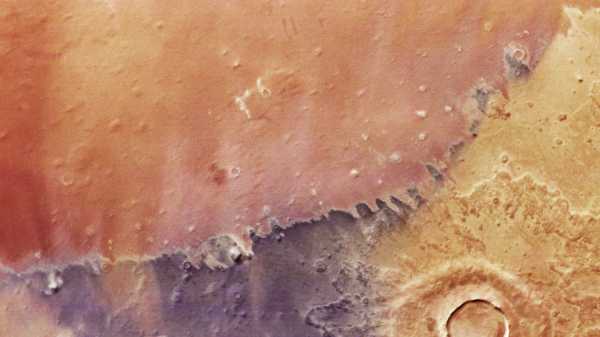

У незвичайному випадку білий марлін (на фото вище) проткнув дзьобом голову чоловіка. (Зображення: LUNAMARINA via Getty Images)

Чому Марс виглядає фіолетовим, жовтим та помаранчевим на приголомшливому новому супутниковому знімку ЄКА?